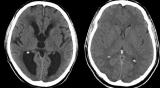

Нарушение оттока жидкости из мозговой ткани связано с дефектом эпендимы. При гидроцефалии, встречающейся у одного из 2000 новорожденных, мозговая жидкость задерживается в камерах головного мозга...